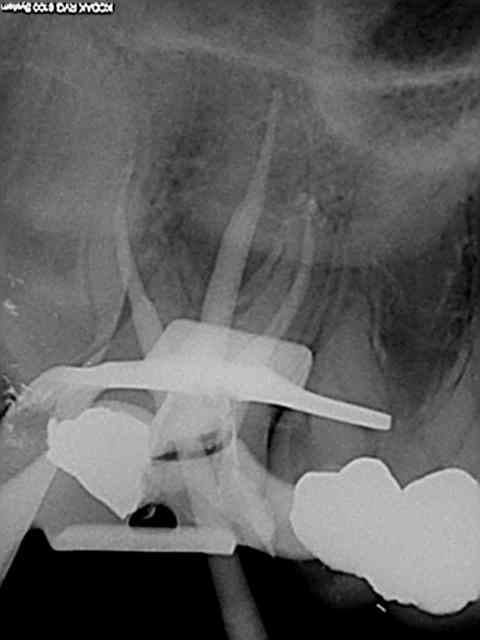

90 mn 2 molar endo + extrac 38. Un peu lent du à la difficulté à anesthésier (30 mn). les crochets apicaux traités comme si ils n'existaient pas avec le r25.